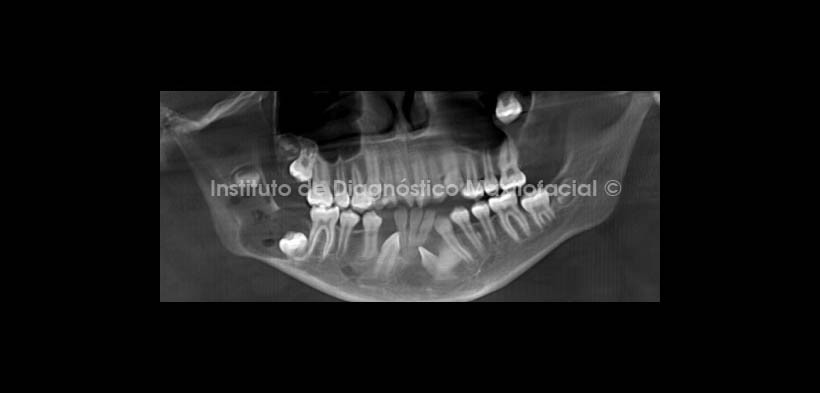

Al estudio tomográfico volumétrico (CBCT) mediante cortes axiales (Fig. 2), reformación panorámica (Fig.3) y reconstrucciones 3D (Fig. 4) apreciamos lesiones isodensas localizadas en el maxilar superior: a nivel de la corona de la pieza 2.8, la misma que se encuentra desplazada cefálicamente.

En el maxilar inferior a nivel coronal de las piezas 3.2 y 4.3, que se encuentra impactada en posición mesioangular, y a nivel del cuerpo y rama mandibular del lado derecho, provocando leve expansión de la tabla ósea lingual y desplazamiento cefálico de la pieza 4.8 así como caudal con aparente impactación de la pieza 4.7.